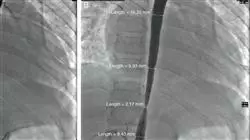

Finalmente, se examinarán técnicas avanzadas de imagenología, como la angiografía rotacional y otras tecnologías de imagen emergentes, aplicadas a las cardiopatías congénitas en adolescentes y adultos. Igualmente, se ahondará en el tratamiento de las arterias pulmonares en estos pacientes, pudiendo interpretar imágenes complejas y realizar procedimientos técnicos fundamentales para tratar las cardiopatías.

En el ámbito de la cardiología pediátrica, el Cateterismo Cardíaco es una técnica diagnóstica y terapéutica de gran importancia para el manejo de las cardiopatías congénitas y adquiridas. Sin embargo, el uso de esta técnica en pacientes pediátricos y adolescentes presenta ciertas particularidades que requieren de una capacitación especializada. El Curso Universitario en Cateterismo Cardíaco Pediátrico y en la Adolescencia te permitirá dominar los instrumentos y métodos más avanzados para el uso de esta técnica en pacientes pediátricos y adolescentes. Durante esta titulación, adquirirás conocimientos avanzados en el manejo de complicaciones, la selección de pacientes y el uso de técnicas intervencionistas mínimamente invasivas.